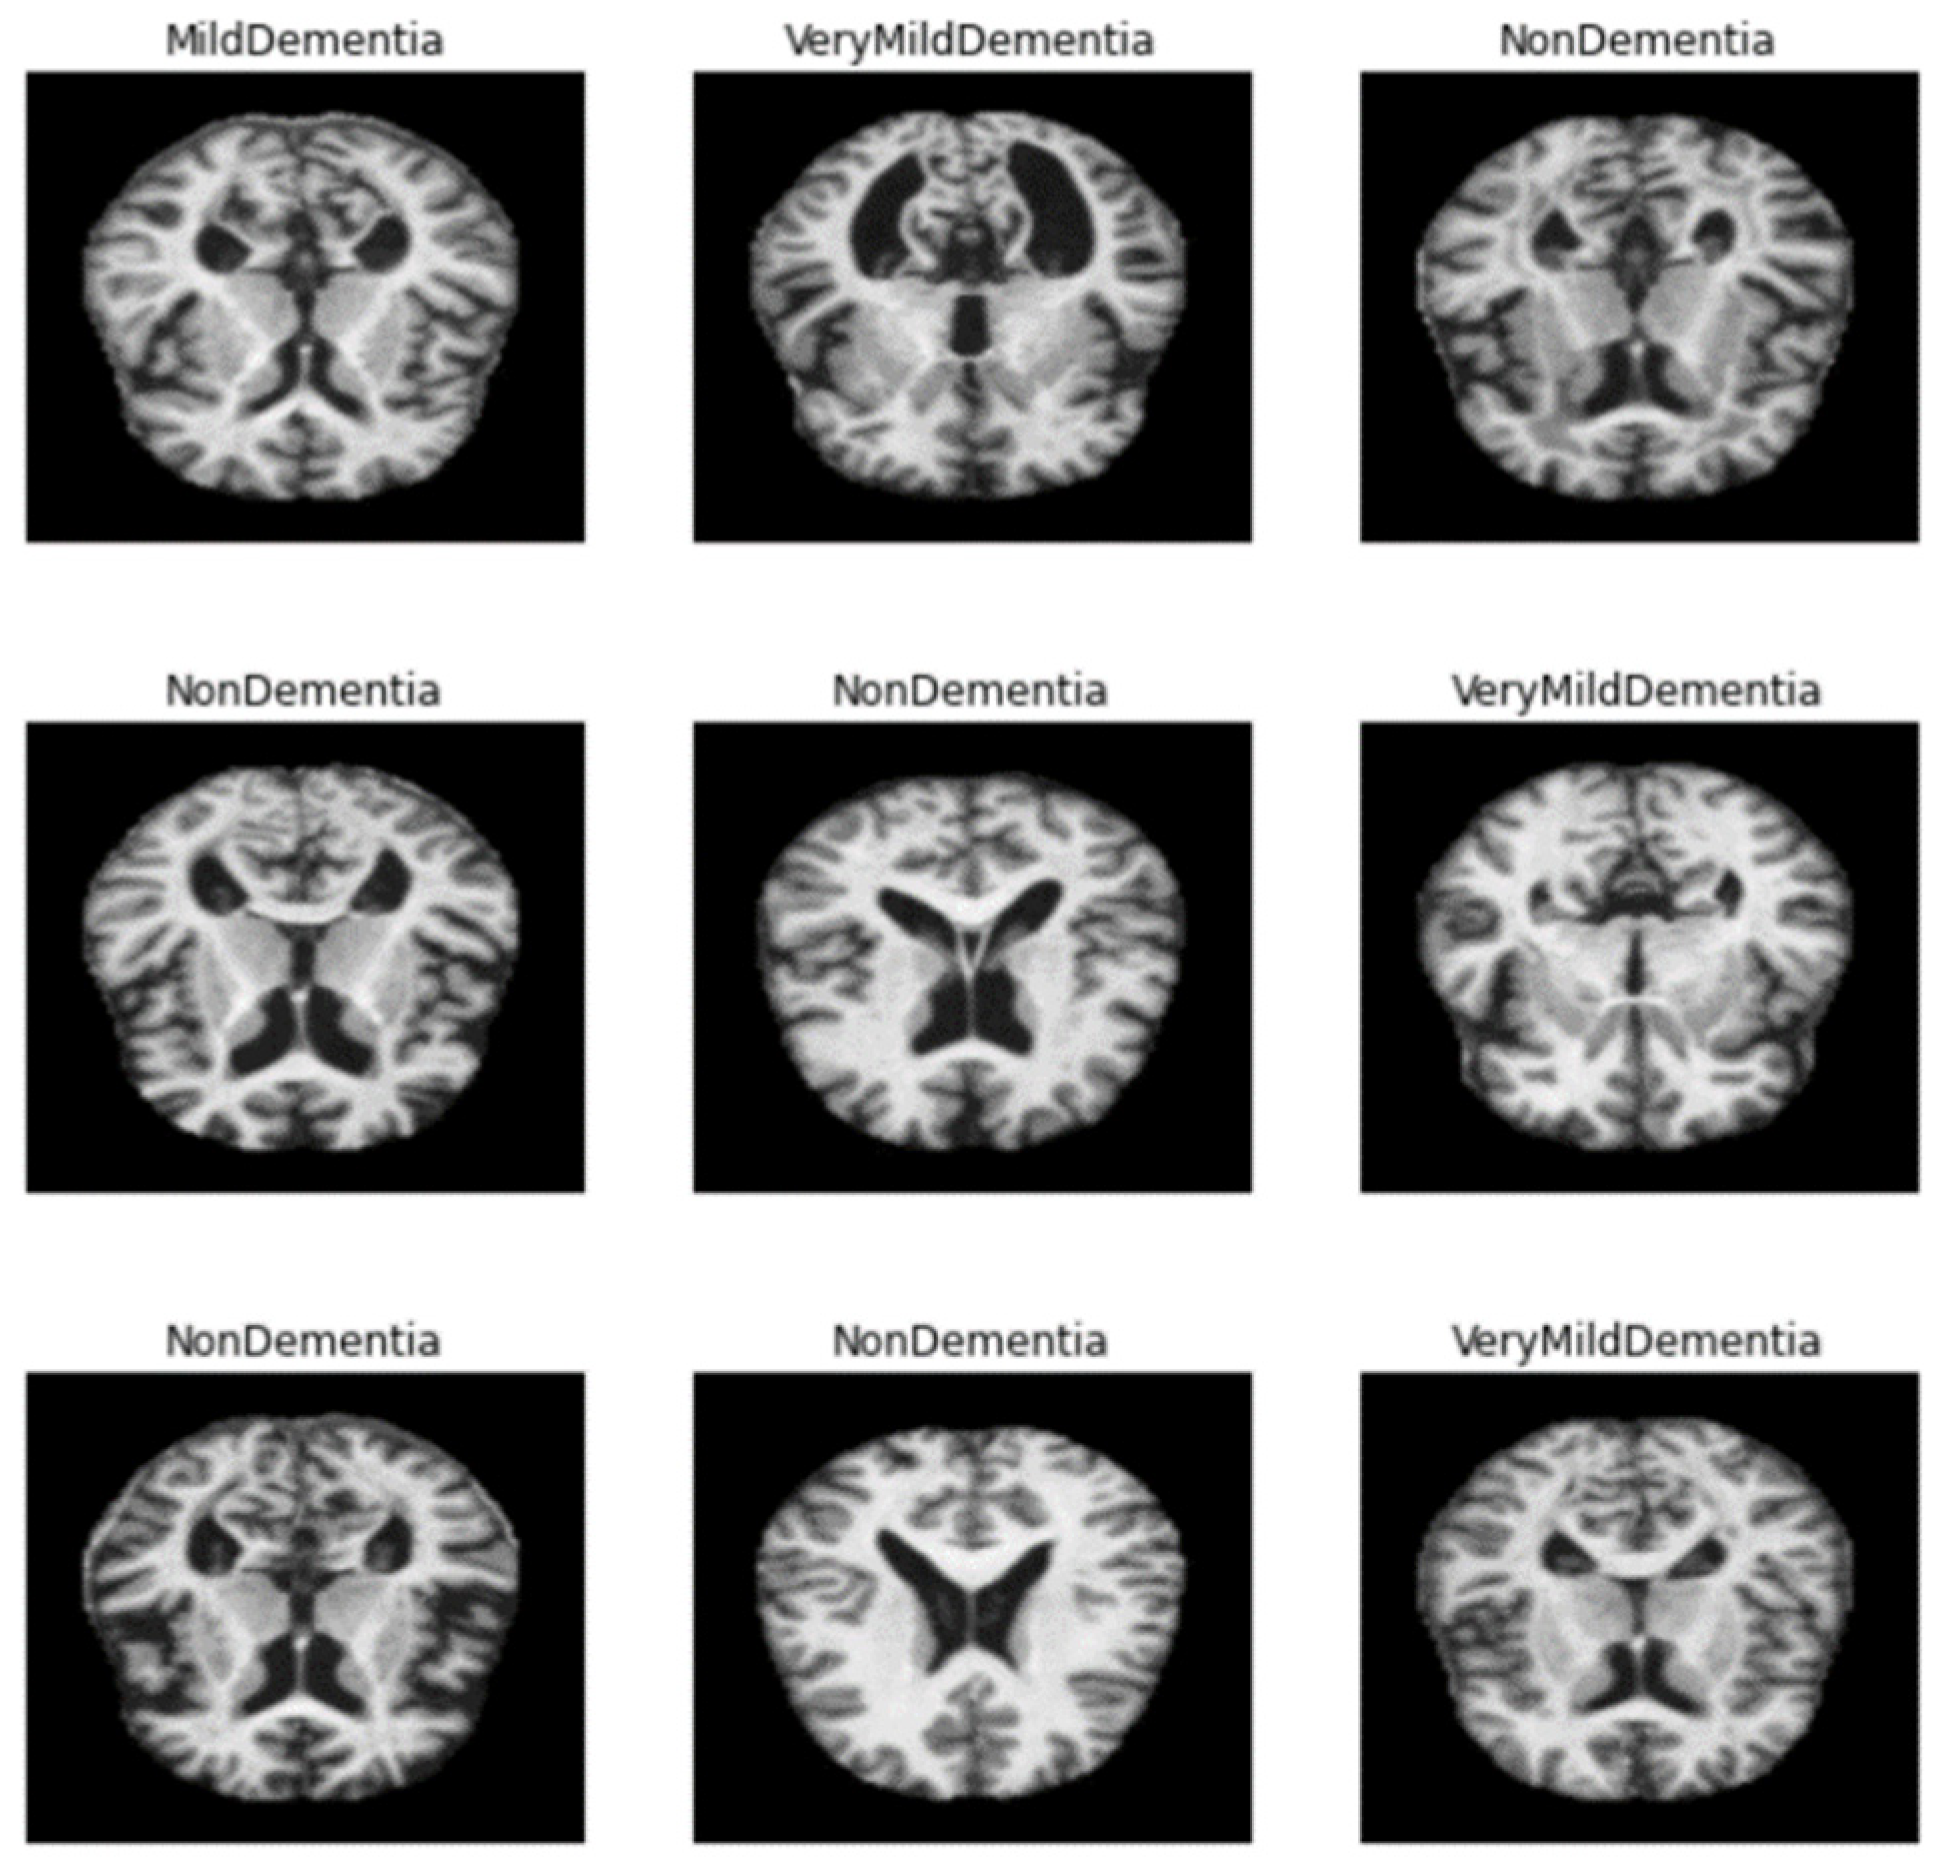

- As mentioned above, the method of diagnosing AD on MRI images compares the size of the hippocampus. However, due to the nature of the existing CNN model, it is difficult to detect because it is not sensitive to image dispersion. Therefore, additional processing of the color space of the image is required.

- The size space of pixels constituting the Alzheimer’s MRI data set is [0, 255]. Among them, patients with AD with reduced hippocampus will have more pixels close to zero than normal people. On the premise of this, the average value of pixel intensities in each MRI image is set as a threshold value. Alzheimer’s should recognize changes in size contraction rather than changes in brain function. Based on this information, it is necessary to set the space as an important feature for the color information of MRI rather than a feature representing the shape of the brain.